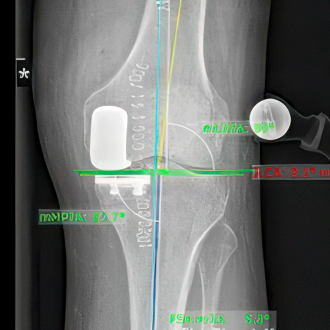

Knieendoprothetik

Dank roboterassistierter Kniechirurgie lassen sich Implantate besonders präzise einsetzen und die Funktion des Gelenks nachhaltig verbessern.

Röntgenaufnahme eines Kniegelenks mit eingezeichneter Achs- und Prothesenplanung.